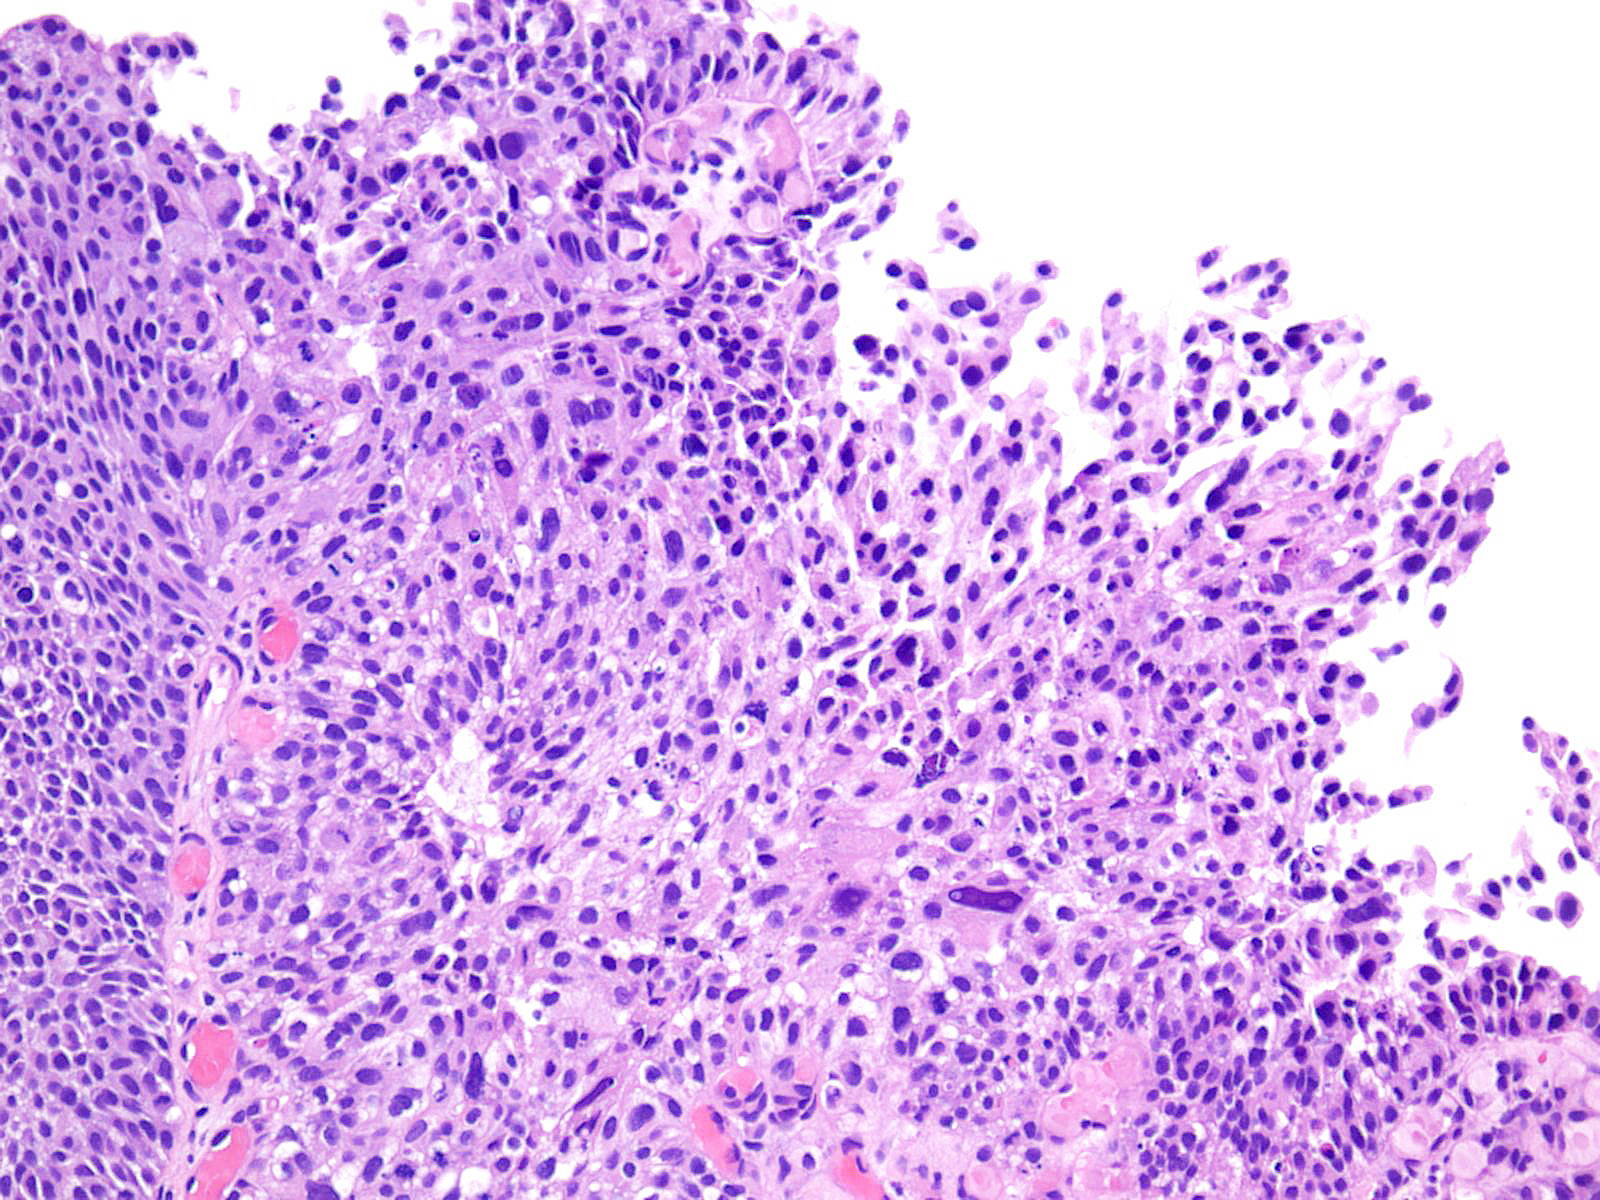

Bladder Papillary Lesions

Case ID: 193